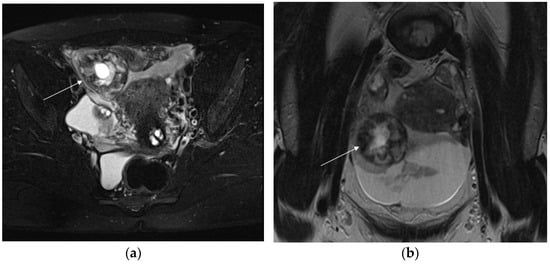

The key MRI feature of EP is an adnexal mass corresponding to the gestational sac, which appears as well-demarcated and thick-walled cystic structure separate from the ovary. The thick wall typically shows a “three rings appearance”; the outer and inner ring are thin and hypointense, whereas the middle ring is thick, displaying heterogeneous signal intensity on T1- and T2-weighted images (WI), due to intramural hemorrhages [41]. Nischio et al. observed this feature in 84–96% of cases [42]. The GS-like structure may contain non-specific fluid without solid components, resulting in hypointensity on T1WIs and hyperintensity on T2WIs, or blood, exhibiting different signal intensities based on the time of bleeding (Figure 1).

Sometimes the GS contains papillary solid components, indicating remnant of fetoplacental tissues, isointense on T2WI [38,41]. If no solid contents are depicted but only blood or fluid–fluid level on MRI, the embryocardia beats could be undetectable on US, indicating death of the embryo due to ectopic implantation. The cystic mass may exhibit heterogeneous peripheral enhancement, corresponding to the sonographic “ring of fire” sign.

Other findings include isolated hemoperitoneum, hemosalpinx and tubal wall enhancement. Hemoperitoneum, appears as fluid high signal intensity on T1WI with fat suppression and as area of heterogeneous signal intensity on T2WI. Hemosalpinx occurs after implantation of the fertilized ovum into the epithelium of the fallopian tube: a dilated tube, filled with high-signal-intensity fluid, is commonly observed on T1WI. Each of these indirect signs in patients with positive pregnancy test results and empty uterine cavity are highly suggestive of EP, even if extrauterine GS is not clearly detectable [43].